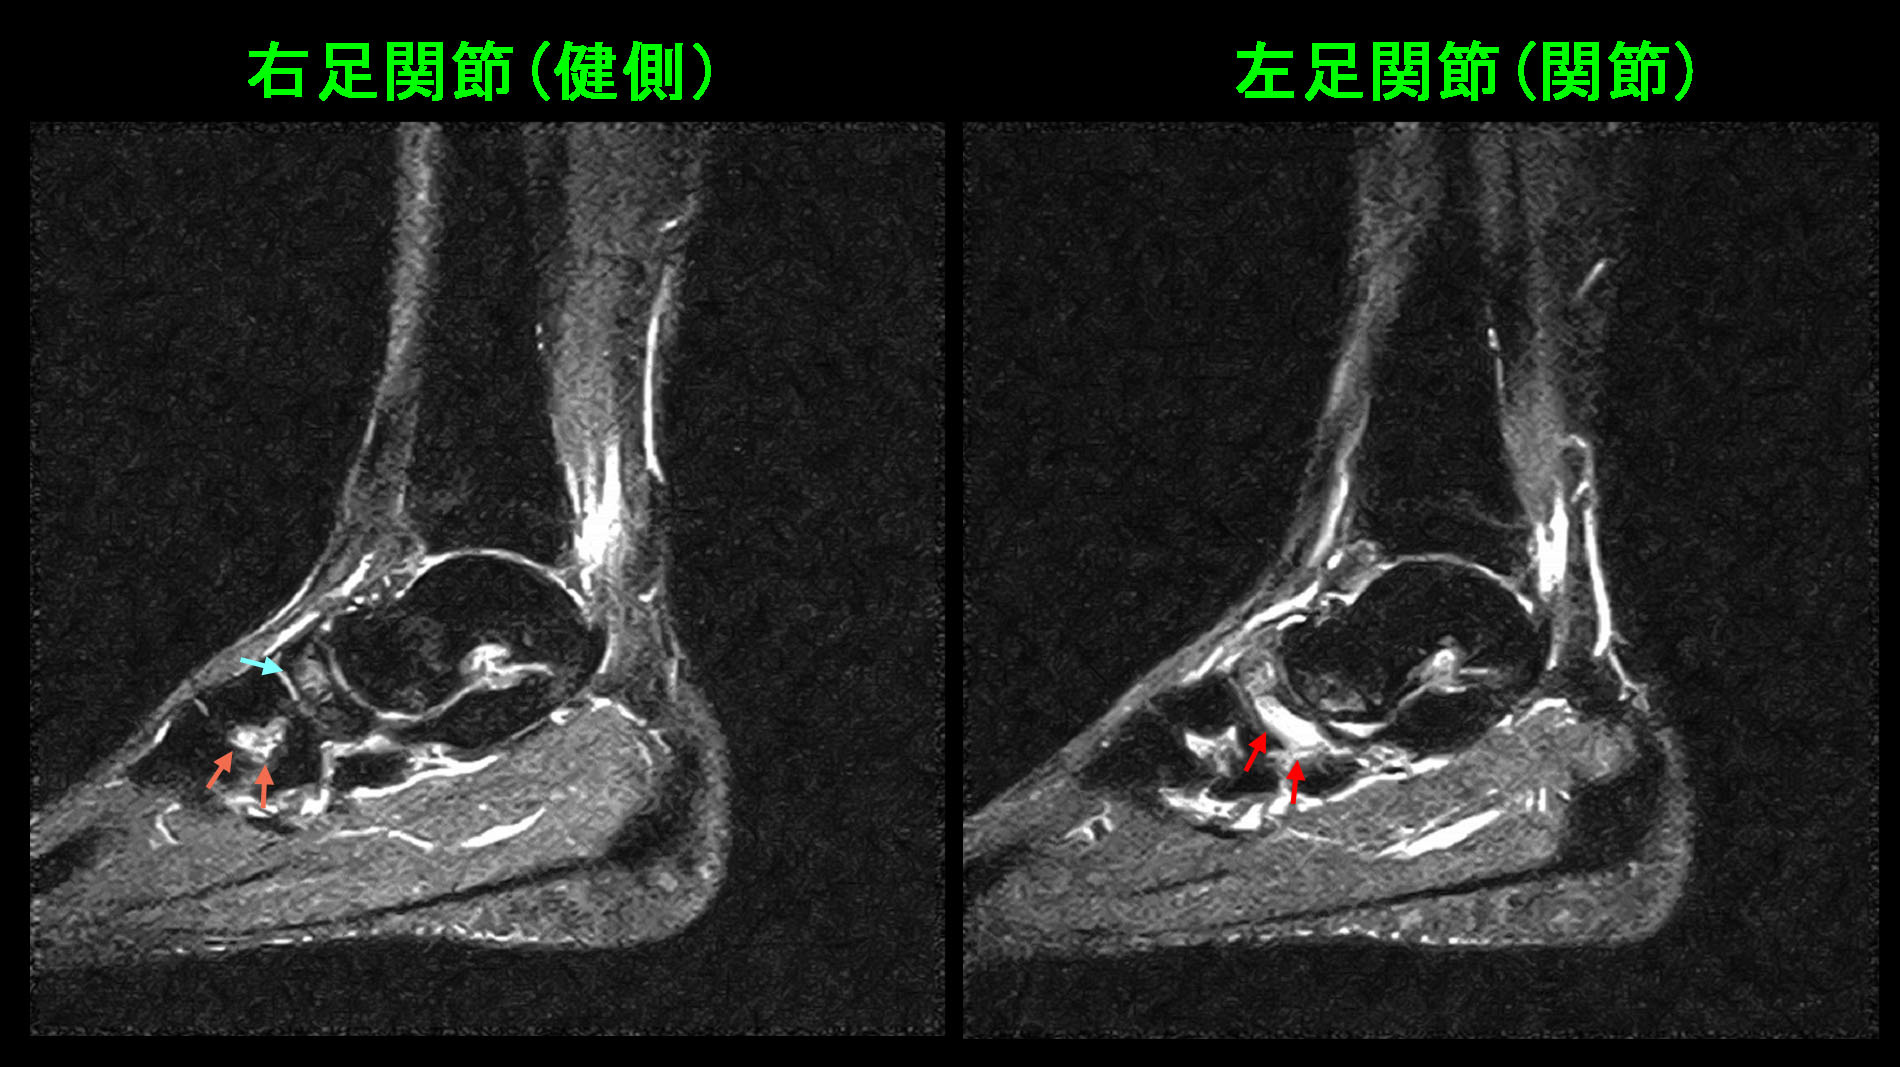

18才男 サッカー舟状骨MR.jpg

MRI画像では、左足関節の赤矢印の部分(舟状骨という骨です)が白くなっていて(高輝度所見で)疲労骨折と診断できます。健側の右舟状骨も青矢印で軽微な高輝度所見を呈しています。さらにその前方部の第2楔状骨という骨はそれなりの高輝度(オレンジ矢印)ですが、右足関節は痛みを訴えてはいません。即ち、青矢印やオレンジ矢印は疲労骨折の潜在的な状態と理解されます。左舟状骨は1か月前から潜在的疲労骨折から自覚的な痛みを感じさせる軽度の疲労骨折になったのです。そして、7月14日の試合でその症状は増悪し、歩行も困難な痛みとなったと理解されます。